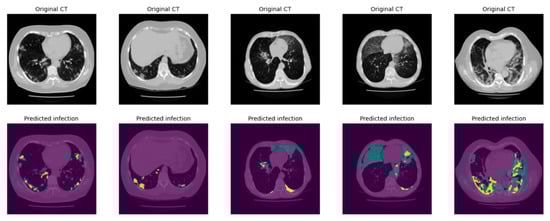

2.3.2. Infection Area Segmentation

2.3.3. Segmentation of GGO and Consolidation Patches